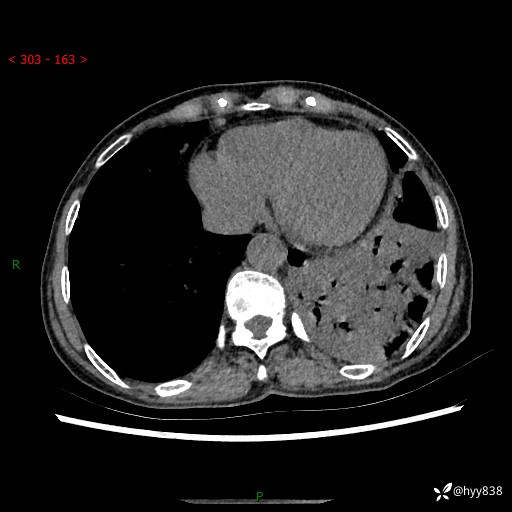

胸部CT平扫+增强